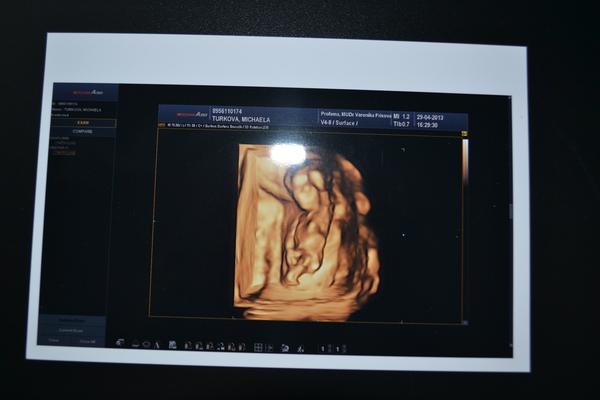

Chlapeček nebo holčička, poznáte to?

Holky prosím, jinou fotku bohužel nemám, jen tuhle z 3D. Poznaly by jste jestli je na fotečce holčička nebo chlapeček? Totiž dva týdny před porodem nám dr. řekl jiné pohlaví než nám tvrdili na genetice a určení pohlaví ve 20 tt 😒 Vůbec nevím na co se teď připravit. Samozřejmě nám je pohlaví jedno, hlavně že je miminko zdravé, ale už máme vše nakoupené, připravené a teď na samém konci tohle to....

@ined77 Holky a podle čeho jste určily, že je to chlapeček? Já tedy vidím hlavičku, zádíčka, kousek zadečku, jednu nožičku. Pohlaví se podle mě určuje podle pohlavních orgánů, které opravdu zezadu nejsou vidět ani u dospělého člověka!

Na fotce od michaela_2 je to podle mě klučina. Pohlavní výběžek směřuje šikmo dopředu, teda tkhle to vidím já.

Tezko rict.

Me to ale prijde jako kluk